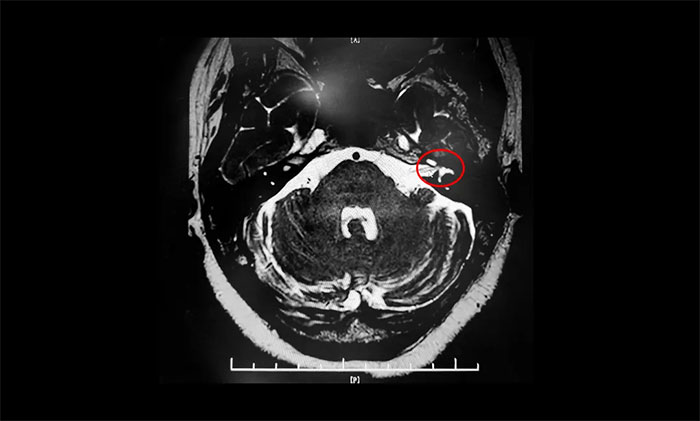

患者王阿姨左侧眼面部抽搐10余年,以眼部最为明显,偶有口角抽搐。起初,症状较轻,未引起重视,后病情加重才就医,经药物、针灸治疗,无明显效果。近两年来,症状持续加重,并影响睡眠。近日,王阿姨慕名求医上海蓝十字脑科医院。面神经MRTA检查,结果示:左侧面神经与周围小血管关系密切。确诊面肌痉挛,手术指征明确。最终,杨忠旭博士顺利为其行微血管减压手术。

▲ 左侧面神经与周围小血管关系密切